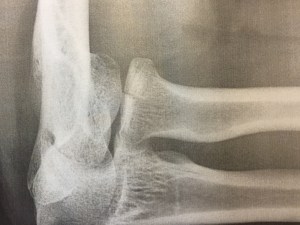

Värttinäluun päässä on tosiaan murtuma, mutta osat ovat paikoillaan. Jos kaikki menee hyvin, niin levolla selvitään. Mutta silti harmittaa. Tämän kesän kiipeilyt ja melomiset taisivat olla nimittäin tässä. Eniten potuttaa, että vamma johtuu pelkästä tyhmyydestä: niistä suojuksista oli sanottu. Mutta kuten kaverini Jani kommentoi: Kovat jätkät eivät käytä suojuksia. Eivätkä kuuntele neuvoja.